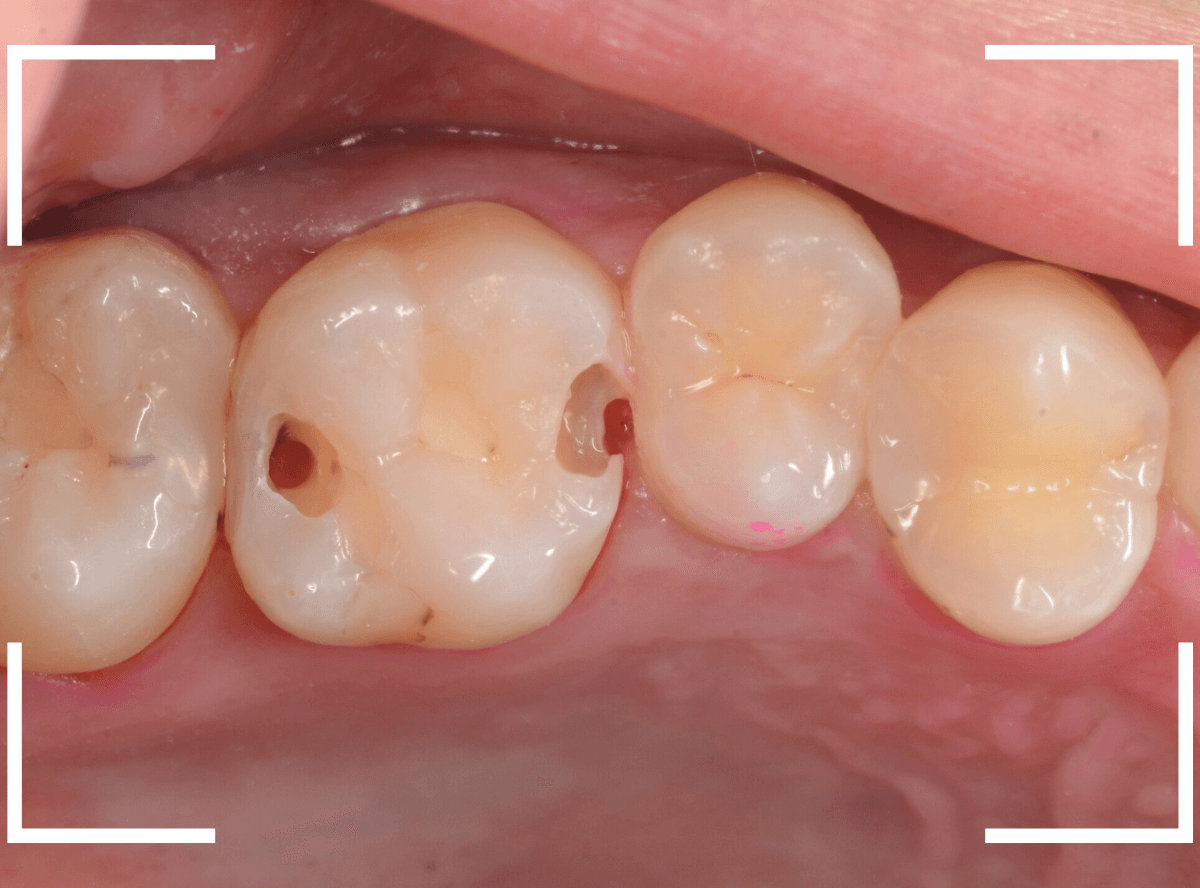

上の奥歯の虫歯が見つかった患者さんです。

初診のチェックの際に、上から目視すると、レジンがつめてある〇部分が薄暗く黒くなっているので、これは虫歯があるな、とわかりました。

レントゲン写真で確認します。

治療を開始します。

先ほどの黒く見えた部分は少し削るとすぐに虫歯が出てきました。

手前の歯まで虫歯を除去した時点で、う蝕検知液で確認します。

赤く染色されている部分が虫歯です。

思ったよりも深めの虫歯ですね。

レジンを除去して虫歯をすべて治療したところです。

レジンの中も全体にうっすらと虫歯になっていました。

このくらいの虫歯でも、患者さんは自覚症状はありませんでした。

ご自身の自覚症状だけでは、虫歯の状況がわからないですし、自然に虫歯が治る事もありません。

いつものお話ですが、定期的なメンテナンスで、虫歯の早期発見・治療を心がけましょう。